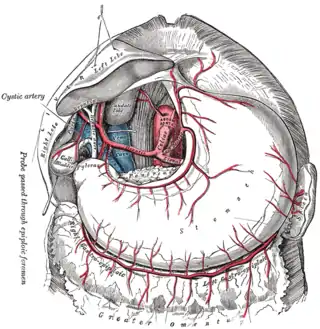

Tronco celíaco con sus ramas. El tronco celíaco es visible en el centro. | ||

Existen tres divisiones principales de la arteria celíaca (arterias: gástrica izquierda, esplénica y hepática común). A continuación se muestra la arteria celíaca con sus sucesivas ramas, las ramas de aquellas y sus respectivas anastomosis.[2]

- Arteria gástrica izquierda(también conocida como Coronaria estomáquica)

- Rama hepática izquierda (inconstante, solo en el 10%), ramas esofágicas y una rama fúndica anterior

- Arteria esplénica

- Arteria gástrica corta

- Arteria gástrica posterior

- Arteria gastroomental izquierda

- Arteria hepática común

- Arteria hepática propia

- Arteria gástrica derecha (anastomosis con arteria gástrica izquierda)

- Arteria cística

- Arteria gastroduodenal

- Arteria pancreatoduodenal superior anterior (anastomosis con arteria pancreatoduodenal inferior)

- Arteria pancreatoduodenal superior posterior (anastomosis con arteria pancreatoduodenal inferior)

- Arteria gastroomental derecha (anastomosis con arteria gastroomental izquierda)